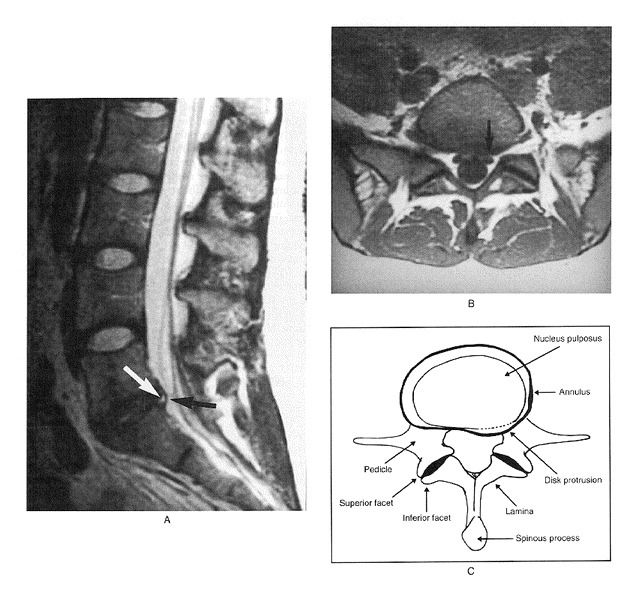

Here are two MRI’s from the study showing a disc protrusion and a disc bulge in two young women with no back pain.

In the discussion section of the study, it states that only 36% of those examined had a normal disc at all levels,

We found a high prevalence of abnormalities in the lumbar spine on MRI examination of people without back pain.

Only 36% of those examined had a normal disc at all levels.

About half had a bulge at at least one intervertebral disc, and about a quarter had at least one disc protrusion.

Given the high prevalence of back pain in the population, the discovery of a bulge or protrusion on an MRI scan in a patient with low back pain may frequently be coincidental.

Therefore, the clinical picture should be correlated with the MRI results.Abnormalities of the lumbar spine by MRI examination can be meaningless if considered in isolation.

Conclusion: An MRI on its own says nothing about your back pain.